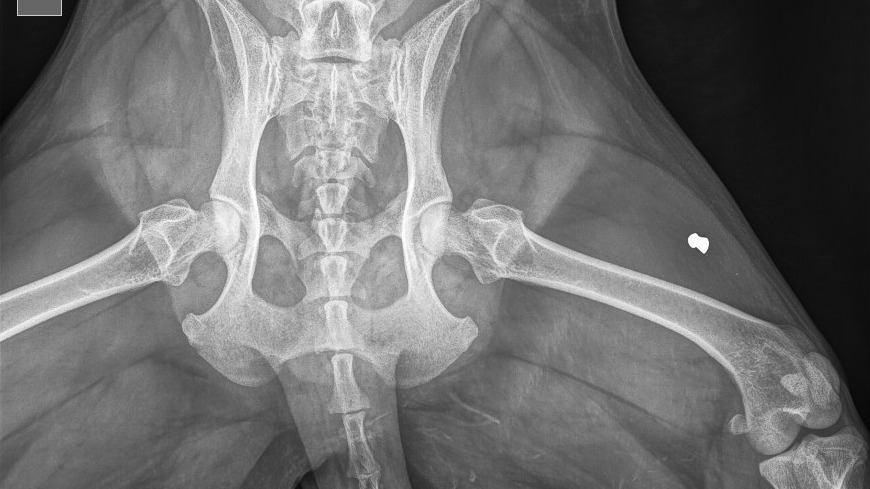

В тот же день женщина отвезла питомца в ветеринарную клинику. Во время обследования выяснилось, что свинцовая пуля формы «юбочка» застряла у собаки в мышце и ее слишком травмоопасно вытаскивать, в связи с чем поражающий элемент так и остался в ноге животного.